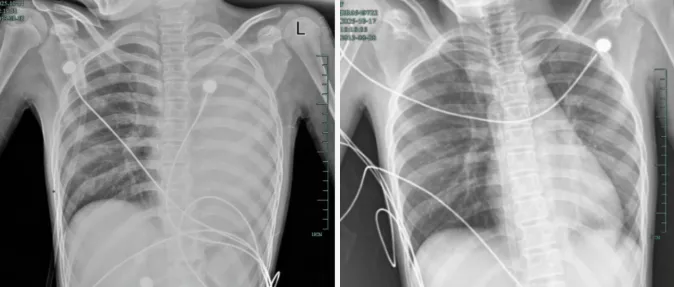

治疗前后影响对比,左肺从“白肺”到正常状态。

据介绍,笑笑一开始只是轻微咳嗽,发热到38℃,检查提示肺炎、肺不张,转诊到浙大四院儿科时,病情已经急剧恶化,出现呼吸急促、胸闷胸痛,体温38.5℃,只能靠5L/min的面罩吸氧维持血氧,胸片显示左肺已完全呈“白肺”改变,肺部炎症进展迅猛。